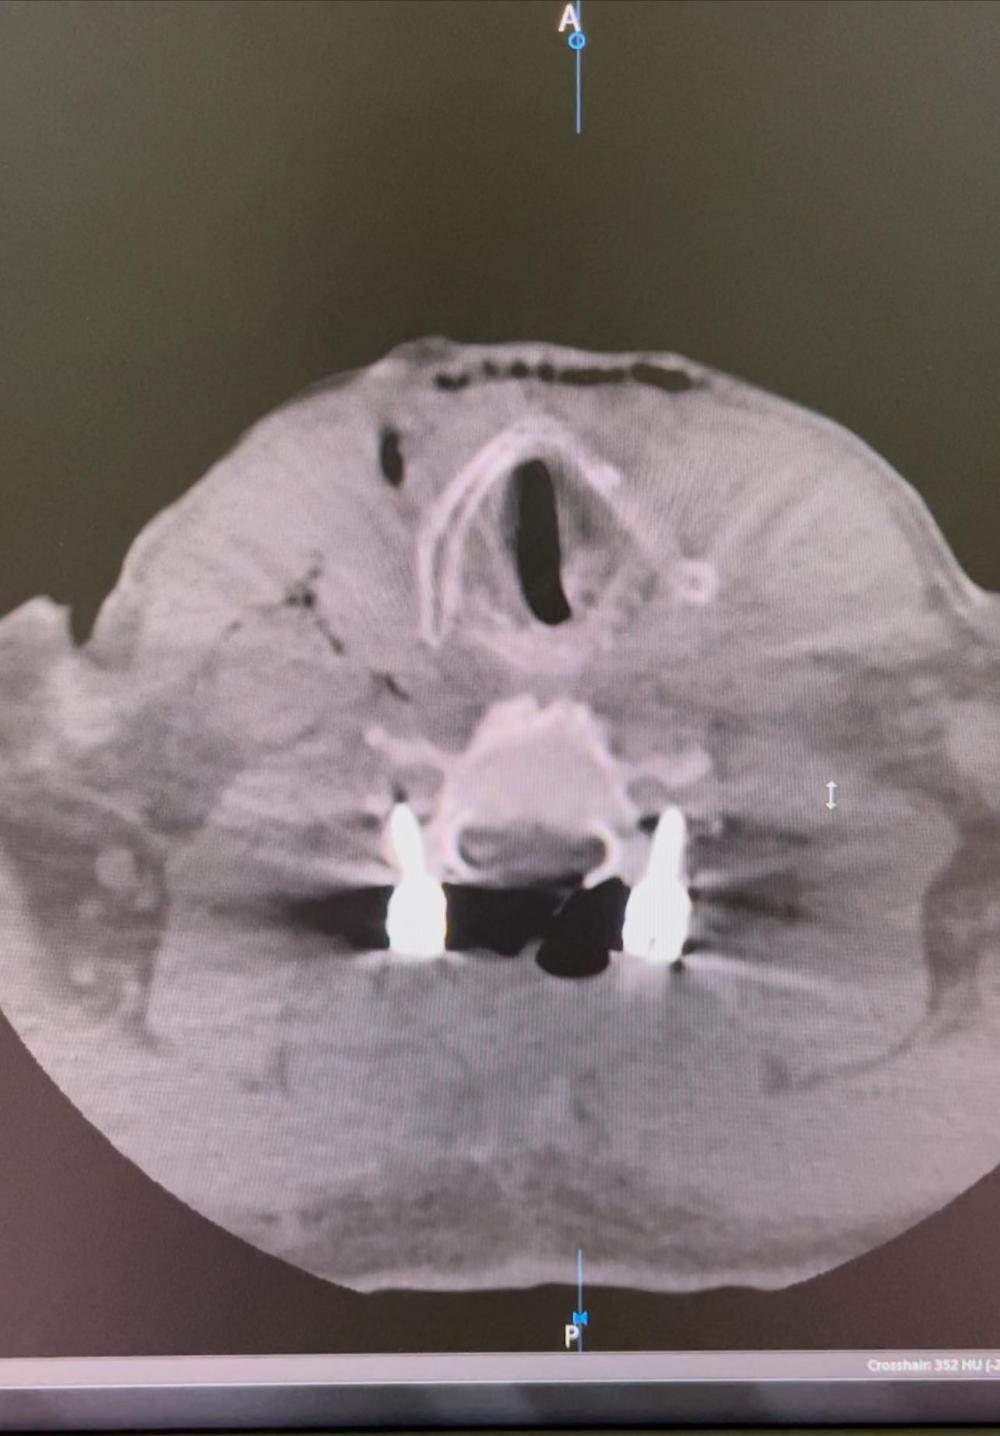

За словами медика, постраждалому було проведено КТ шийного відділу хребата та діагностовано ускладнену хребетно-спінальну травму.

Тому прийняли рішення про проведення операції-стабілізації 360 градусів переломовививиху С6-С7.

"Перший етап полягав в усунення вивиху та проведення задньої стабілізації. Під час другого - провели передній корпородез. Пацієнта перевернули на спину, виконали передню дискектомію С6-С7, встановили кейдж на рівні С6-С7 та зафіксували передньою пластиною гвинти (15мм,) імплантовані у тіла С6-С7", - розповів нейрохірург.